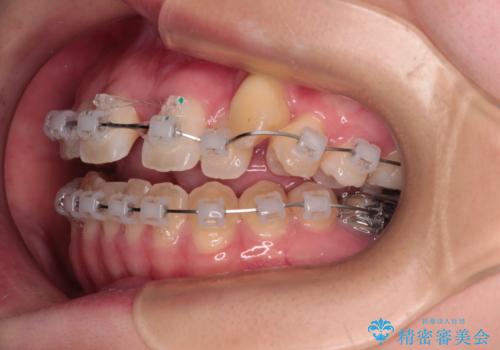

- クリアブラケット

上顎骨を拡大することで、八重歯やデコボコを歯列に収めることができ、下顎の歯が外に位置していた奥歯の咬み合わせも改善することができました。

スペースも短期間に獲得できるため、1年程度で治療を終えることができました。